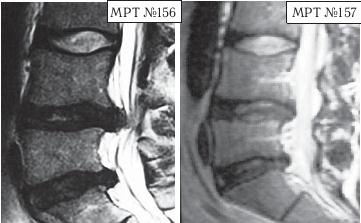

На МРТ № 154 наблюдается состояние поясничного отдела позвоночника после двух операций в сегментах LIII-LIV и LV-SI секвестрированная грыжа межпозвонкового диска в сегменте LIV-LV, абсолютный стеноз спинномозгового канала. На МРТ № 155 — состояние поясничного отдела позвоночника после лечения методом вертеброревитологии. А в этом случае пациента привезли в клинику с целым «букетом» заболеваний позвоночника. ![]() На МРТ № 156 наблюдается состояние поясничного отдела позвоночника после операций: рецидив грыжи межпозвонкового диска в сегменте LIV-LV, абсолютный стеноз спинномозгового канала на этом уровне, спондилёз, эпидурит, арахноидит, наблюдается грыжа межпозвонкового диска в сегменте LV—SI. На МРТ № 157 — состояние поясничного отдела позвоночника после лечения методом вертеброревитологии. Обратите внимание на процессы репаративной регенерации в межпозвонковых дисках в сегментах LIV-LV и LV-SI после лечения данным методом. Следующий случай также по-своему уникален. Это ещё одно прямое свидетельство широкого спектра возможностей вертеброревитологии в решении задач, многие из которых на современном этапе медицины считались неразрешимыми.